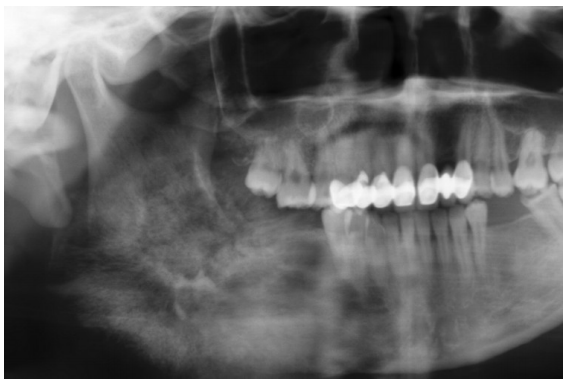

54. 承上題,拔牙前所照的環口攝影(panorex),卻意外發現病人的上下顎骨有瀰漫性放射 線透視影像(generalized rarefaction) ,經抽血檢查發現:Calcium 的濃度在正常範圍; Phosphorus 的濃度明顯上揚;Alkaline phosphotase 也上升。請問最合理的解釋為何? (A) Primary Hyperparathyroidism (B) Secondary Hyperparathyroidism (C) TertiaryHyperparathyroidism (D) Osteoporosis

55 (A) LeFort III +雙側 zygomatic complex fracture +雙側 blowout fracture (B) LeFort I +雙側 zygomatic complex fracture +雙側 blowout fracture (C) 右側 mandibular condylar neck fracture +雙側 zygomatic complex fracture +單側 blowout fracture (D) 左側 mandibular body fracture +雙側 zygomatic complex fracture +單側 blowout fracture

56. 承上題,若症狀如下:雙側臉頰腫脹、雙側眶下及上唇、鼻翼等區域麻木感,雙側眼眶 周圍瘀青、雙側眼結膜下出血、複視、咬合不正,最可能的診斷為何? (A) 雙側 zygomatic complex fracture (B) LeFort I fracture (C) 單側 zygomatic complex fracture +單側 blowout fracture (D) LeFort II +雙側 blowout fracture